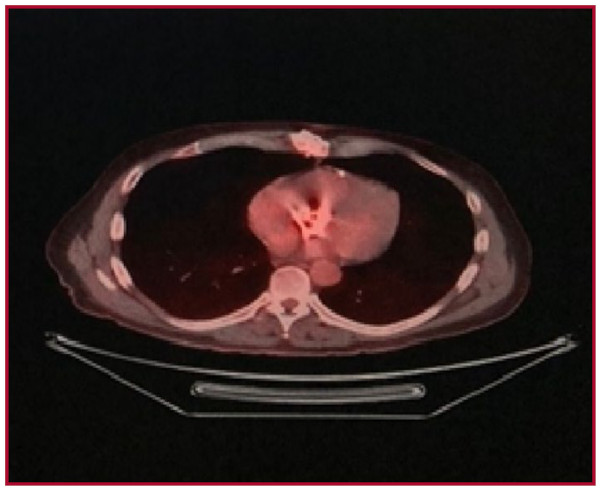

Por sospecha de afectación de la válvula protésica se realiza de forma ambulatoria tomografía por emisión de positrones/tomografía computarizada (PET /TC) que evidencia moderada captación difusa del radiotrazador en la topografía del reemplazo valvular aórtico, lo cual en ausencia de foco hipercaptante dominante y SUV max 3,5 sugiere ausencia de proceso infeccioso activo (Figura 3).

La utilidad de la PET/TC es relevantemente mayor en la endocarditis de válvula protésica que en la endocarditis infecciosa de válvula nativa, y es una excelente alternativa, en caso de estudios ecográficos negativos o dudosos. La integración de la PET/TC como una herramienta diagnóstica en la endocarditis, permite reclasificar al 76% de los pacientes con endocarditis infecciosa válvula protésica de “posible” a “definitiva” 5